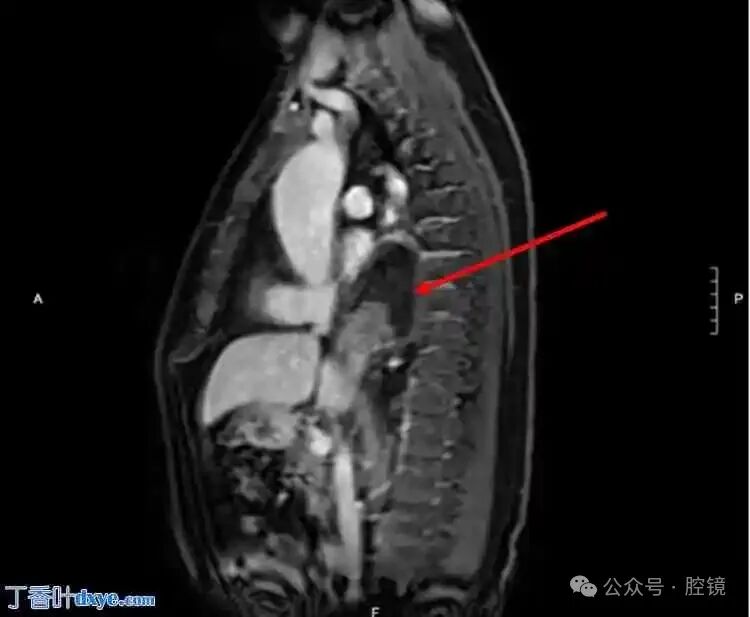

A 65-year-old male presented to the emergency department with a complaint of upper abdominal pain for 48 hours, radiating to the back. His medical history indicated a 5 cm ascendingaortic aneurysm. The patient had no previous surgical history and no significant family history. He exhibited no fever, normal blood pressure, and tachycardia. Physical examination revealed tenderness in the upper abdomen with muscle rigidity, but no rigidity or rebound tenderness. A non-contrast spiral abdominal CT scan showed a soft tissue mass just above the gastroesophageal junction, requiring differential diagnosis with a lipoma or liposarcoma (Figure 1-2). Due to the unclear diagnosis, the physician arranged for a chest MRI. The MRI revealed a large omental hernia through the esophageal hiatus (Figure 3-4), with fluid around the herniated omentum, suggesting strangulation. In the sagittal view of the MRI, the abdominal omentum was seen entering the thoracic cavity (Figure 2-4).Figure 1. Cross-sectional view showing a lipomatous mass behind the heart, with surrounding fluid consistent with strangulated lesions.

Figure 3. Cross-sectional view of the omentum in the thoracic cavity.